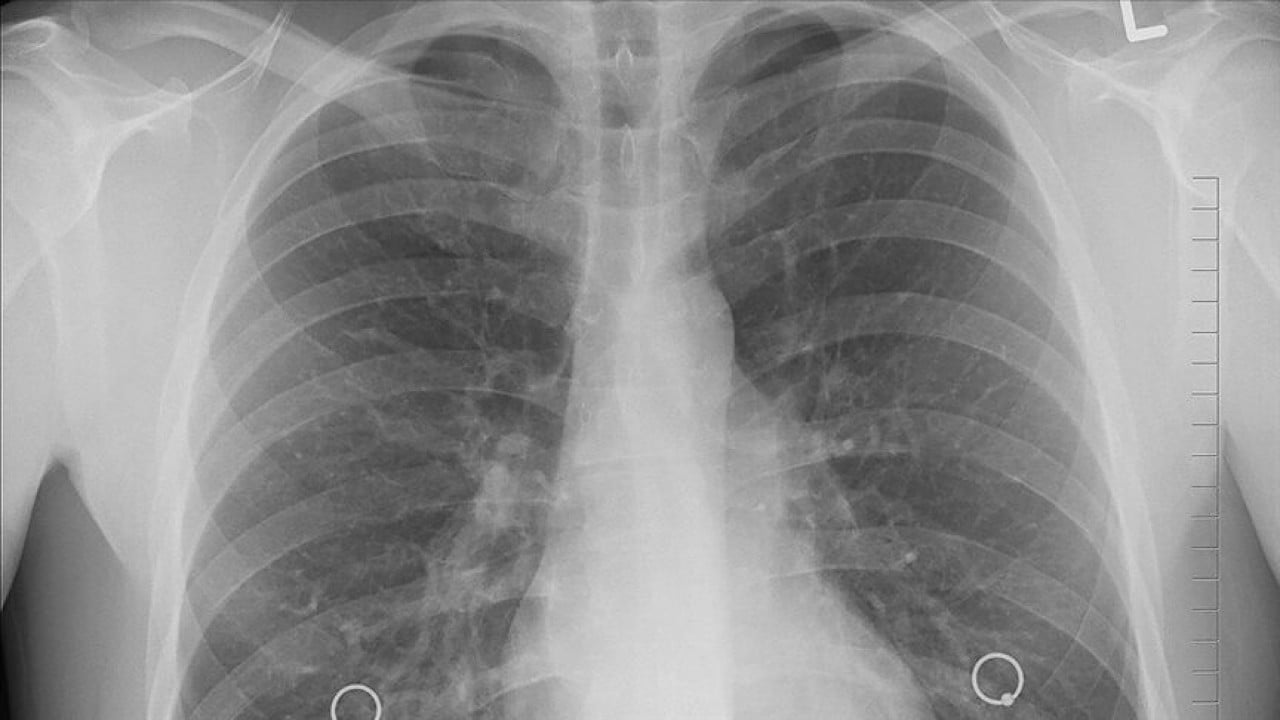

Bir nefeslik şifa: İç çekmek akciğerleri iyileştiriyor

Yeni araştırma, derin nefeslerin akciğerleri daha esnek hale getirerek solunumu kolaylaştırdığını ortaya koydu. Zürih Federal Teknoloji Enstitüsü (ETH) liderliğindeki ekibin "Science Advances" adlı bilimsel dergide yayımlanan makalesine göre, derin nefes alıp vermek akciğere esnekliğini yeniden kazandırmada kritik bir rol oynuyor.

Temel olarak, akciğer nefes alındığında genişler, verildiğinde ise küçülür. Bu hareket sırasında organın dokusu ve yüzeyi bir direnç gösterir. Çalışma, özellikle derin nefeslerden sonra akciğer yüzeyini kaplayan sıvının bu direnci azalttığını gösteriyor. Çalışmanın yazarlarından Jan Vermant araştırma bulgularını "Sıvı tüm yüzeyi ıslatır, bu da akciğerin daha kolay şekil almasını sağlar. Teknik bir ifadeyle, daha esnek hale gelir" diye açıklıyor.

DW'de yer alan habere göre, çalışma kapsamında, akciğer sıvısının farklı senaryolarda nasıl davrandığı incelendi. Laboratuvar ölçümleri, derin soluklardan sonra akciğer yüzeyindeki sıvının yüzey geriliminin belirgin şekilde azaldığını ortaya koydu. Araştırmacılar bunun, derin bir nefes aldıktan sonra göğüste hissedilen ferahlamayı açıklayabileceğini düşünüyor.

Bilim insanları bu durumu, akciğer yüzeyini kaplayan sıvının çok katmanlı yapısıyla açıklıyor. Bu sıvı, akciğerin nefes alırken genişlemesini ve verirken büzülmesini kolaylaştırıyor. Çalışmanın bir diğer yazarı Maria Novaes-Silva'ya göre, ideal yapıda en üst katmanın daha sert, alt katmanların ise daha yumuşak ve hassas olması gerekiyor. Sığ nefes alındığında, sıvı yeterince hareket etmediği için zamanla akciğer yüzeyindeki katmanlı yapı bozuluyor. Buna karşılık, ara sıra alınan derin nefesler bu ideal yapının yeniden oluşmasına yardımcı olabiliyor.

Araştırmacılar, elde ettikleri bulguların, sürekli sığ nefes alma durumunda solunumun giderek zorlaştığını gösteren klinik gözlemlerle paralellik taşıdığını belirtiyor. Elde edilen bulgular, akciğer hastalıklarının tedavisinde yeni yöntemlerin geliştirilmesine kapı aralayabilir.